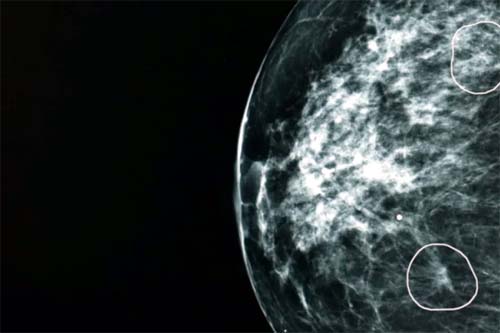

Uma ferramenta de inteligência artificial testada pelo NHS, o serviço público de saúde do Reino Unido, identificou com sucesso pequenos sinais de câncer de mama que não haviam sido detectados por médicos.

A ferramenta, chamada Mia, foi testada em conjunto com médicos do NHS e analisou mamografias de mais de 10 mil mulheres.

Na maioria dos exames, Mia não identificou indícios de câncer, mas sinalizou com sucesso todos aqueles em que havia indícios apontados por médicos antes, além de outros 11 em que os médicos não haviam identificado tumores.

A BBC acompanhou Mia em ação em um hospital do NHS. Foram mostrados à ferramenta tumores que eram praticamente invisíveis ao olho humano. Mas que, dependendo do tipo, podem crescer e se espalhar rapidamente.